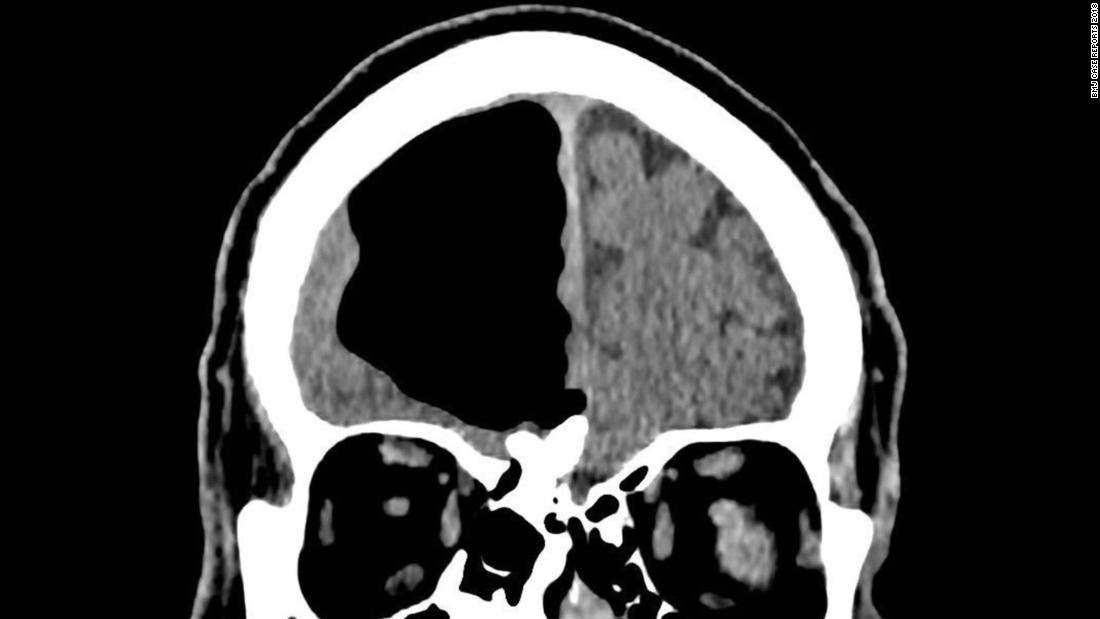

أظهر التصوير المقطعي المحوسب لدماغ المريض وجود جيب كبير من الهواء - يسمى أيضًا القيلة الهوائية - في الفص الأمامي الأيمن للمريض يبلغ طوله حوالي 3 بوصات ونصف.

كان الجيب الهوائي خلف الجيب الجبهي مباشرة وفوق الصفيحة المصفوية، التي تفصل تجويف الأنف عن تجويف الجمجمة.

عندما تكون القيلة الرئوية موجودة في الدماغ، غالبا ما يشار إلى الحالة باسم استرواح الرأس. وقال كوهين إنها في الغالب تضغط على الفص الجبهي، الذي يلعب دورا كبيرا في حركة العضلات الإرادية.